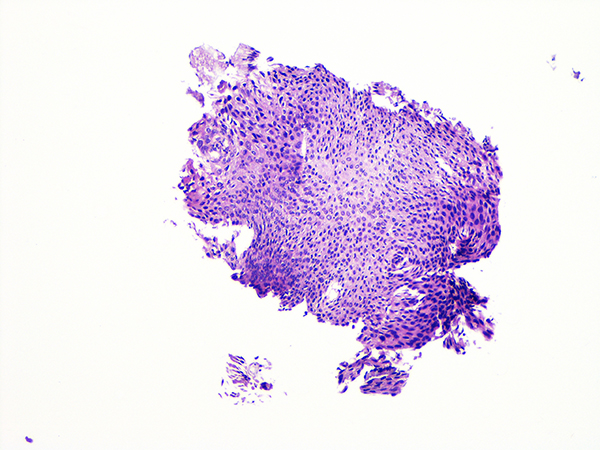

![]() Case 4

Soft Bx CIN 3

10x - Low Power |